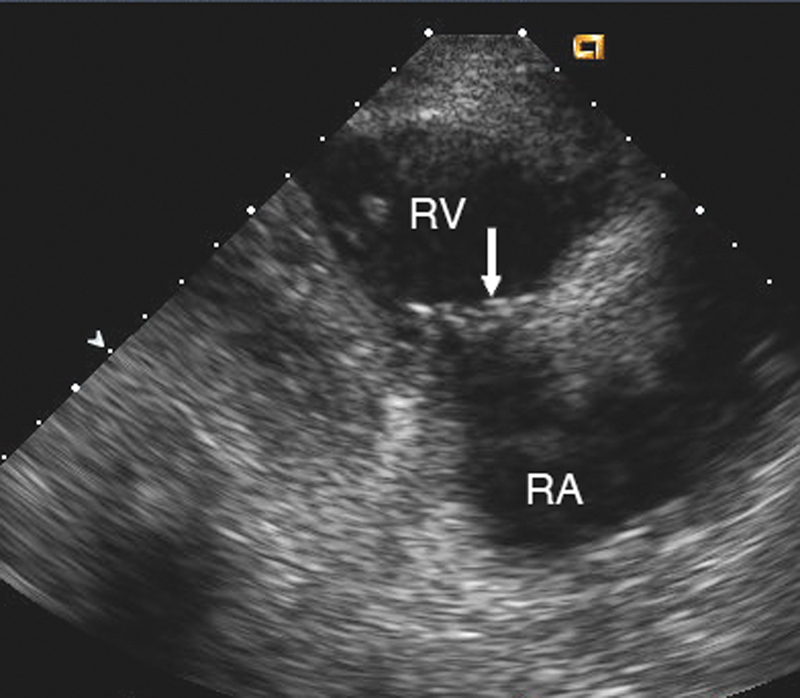

فحوصات تشخيصية لبعض امراض القلب والشرايين التاجية